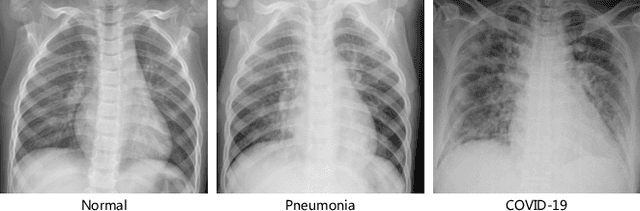

Abstract:The novel 2019 Coronavirus (COVID-19) infection has spread world widely and is currently a major healthcare challenge around the world. Chest Computed Tomography (CT) and X-ray images have been well recognized to be two effective techniques for clinical COVID-19 disease diagnoses. Due to faster imaging time and considerably lower cost than CT, detecting COVID-19 in chest X-ray (CXR) images is preferred for efficient diagnosis, assessment and treatment. However, considering the similarity between COVID-19 and pneumonia, CXR samples with deep features distributed near category boundaries are easily misclassified by the hyper-planes learned from limited training data. Moreover, most existing approaches for COVID-19 detection focus on the accuracy of prediction and overlook the uncertainty estimation, which is particularly important when dealing with noisy datasets. To alleviate these concerns, we propose a novel deep network named {\em RCoNet$^k_s$} for robust COVID-19 detection which employs {\em Deformable Mutual Information Maximization} (DeIM), {\em Mixed High-order Moment Feature} (MHMF) and {\em Multi-expert Uncertainty-aware Learning} (MUL). With DeIM, the mutual information (MI) between input data and the corresponding latent representations can be well estimated and maximized to capture compact and disentangled representational characteristics. Meanwhile, MHMF can fully explore the benefits of using high-order statistics and extract discriminative features of complex distributions in medical imaging. Finally, MUL creates multiple parallel dropout networks for each CXR image to evaluate uncertainty and thus prevent performance degradation caused by the noise in the data.